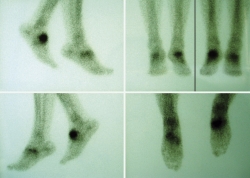

También se hizo un estudio gammagráfico (Figura 4) donde se aprecia un incremento de actividad en la fase vascular, en la fase tisular y en el estudio óseo tardío, lo que indica la presencia de componente inflamatorio añadido a la pseudoartrosis.

Figura 4. Gammagrafía.